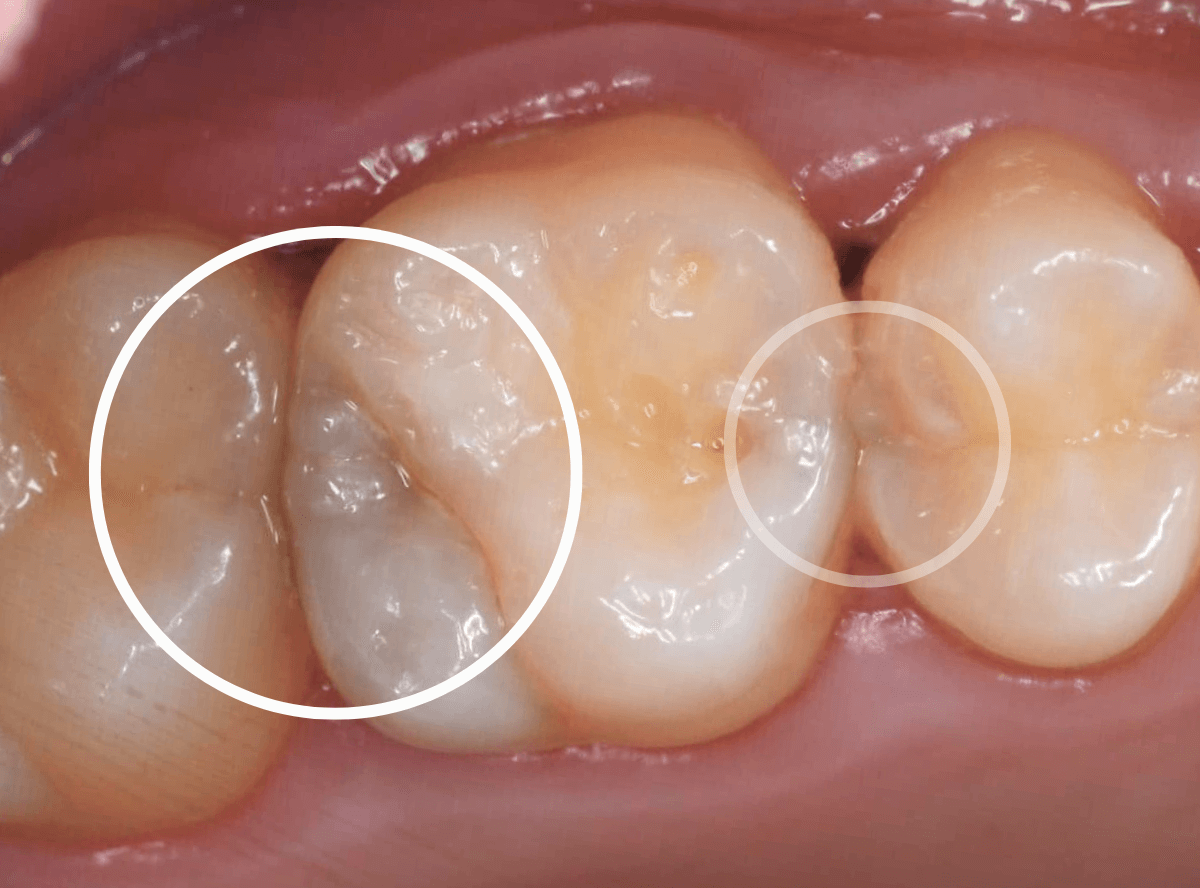

Case.7 定期メンテナンスで虫歯を発見!

メンテナンス時に、虫歯がみつかった患者さんです。

奥(右の〇)側が黒く虫歯が透けて見えますね、割とわかりやすい隣接面う蝕です。

よく見ると手前(左の〇)側も中が白濁してう蝕らしくなっているのがわかります。

レントゲン写真で確認します。

奥側の虫歯は明らかにレントゲンでも確認できますね、手前側の虫歯ははっきりしません。

あとは、虫歯を削りながら確認します。

まずは、奥側の部分から虫歯の治療をします。

少し削ると、落とし穴にはまるように虫歯の部分がでてきました。

最終的に虫歯を除去したところです。

奥の虫歯は、後ろの歯にまで及ぶ虫歯でした。

このように、隣りの歯との間の虫歯は、歯科医院での検査で初めてわかる事が多く、思ったよりも広く深い虫歯になっている事が多いです。